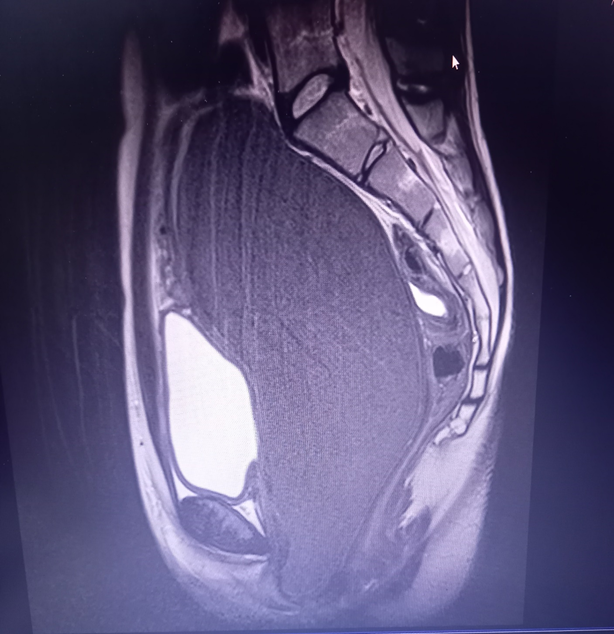

She underwent an abdominal magnetic resonance imaging (MRI) scan, revealing a distended vagina measuring 18.4 x 8.8 x 8.2cm, with a T1 hyperintense and T2 hypointense fluid collection suggestive of hemorrhagic fluid, consistent with hematocolpos. The uterus measured 5.3x5.6x3.5cm and was displaced anteriorly and to the left of the midline (Figure 2) (Figure 3). The rest of the abdominal and pelvic organs, including the kidneys, appeared normal.

Figure 2 Presence of hematocolpos (MRI scan: sagital section).

Figure 3 Presence of hematocolpos and displaced uterus (MRI scan: transverse section).